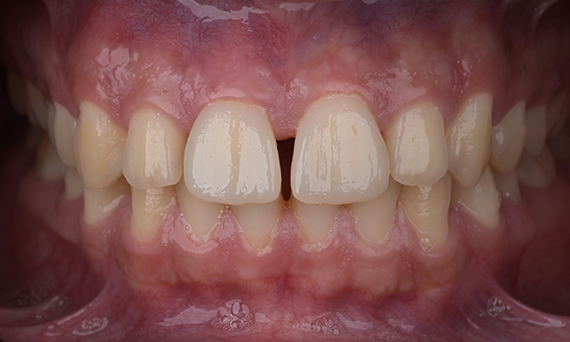

Before: Clinical Situation pre-op. Trauma of upper central incisors

After: Adhesively bonded restorations.